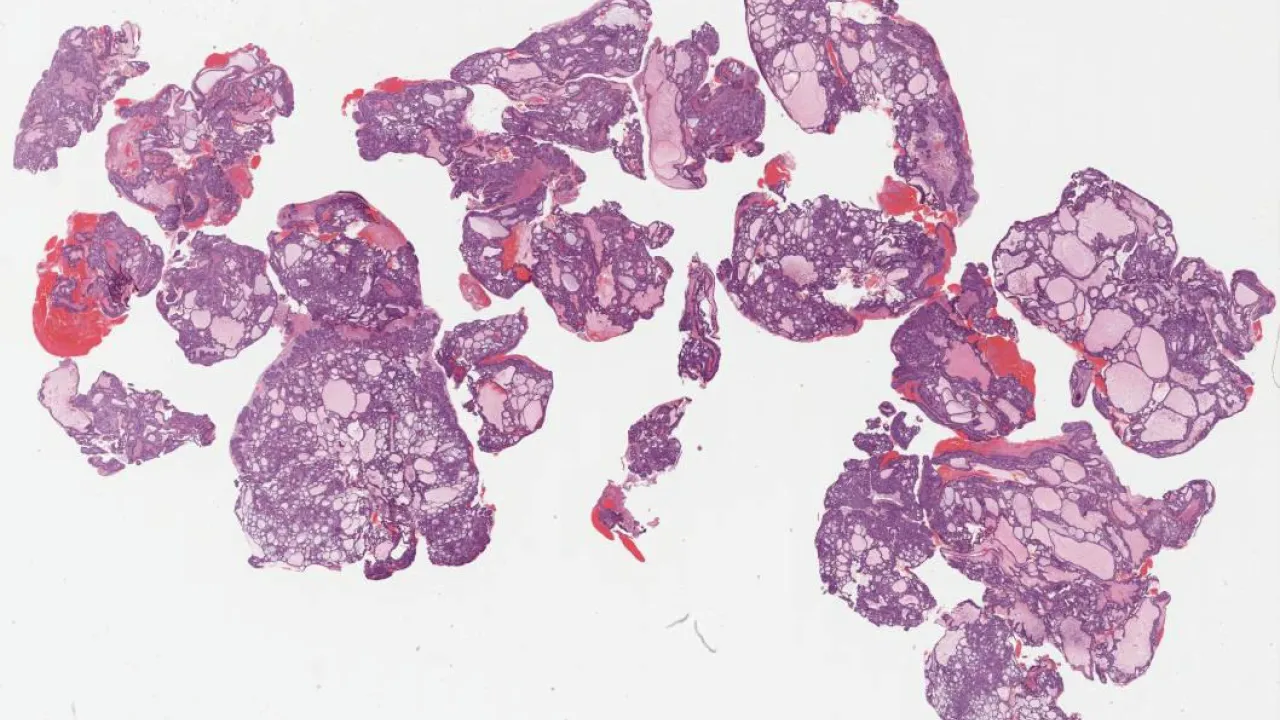

Kidney, Papillary renal cell carcinoma

Lung, Metastatic adenocarcinoma